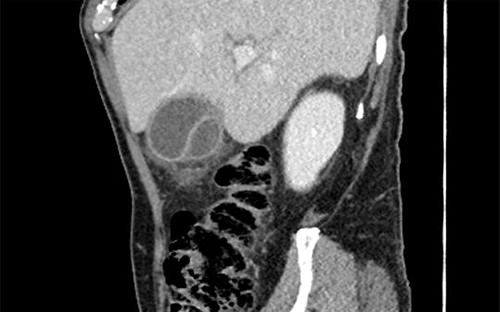

Subsequent review of preoperative imaging solved the mystery. Duplicated gallbladder with double cystic ducts was clearly evident on CT and magnetic resonance imaging (MRI) which were hidden in plain sight (Figs 4–7). CT cholangiogram (Fig. 3) was performed Day 1 post-operatively showing the double cystic duct with no evidence of bile leak. Rest of patient’s admission was uneventful and he was cleared for discharge on Day 5 post-operatively. Patient remains well and was back to his daily activities during his follow-up review.

Preoperative T2-weighted MRCP; double cystic ducts seen upon retrospective review of images post cholecystectomy.

3D reconstruction of duplicated gallbladder and biliary tree from MRCP.